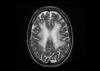

Valorado en urgencias por clínica de debilidad facial izquierda. Comenzó tto con corticoides sin mejoría.  Refiere alteración cognitiva, con despistes y pérdida de memoria desde el día siguiente,...

Neurología: InfecciosasEtiología: Infecciosas / inflamatoria / desmielinizanteDiagnóstico final: leucoencefalopatía multifocal progresivaNivel de certeza: